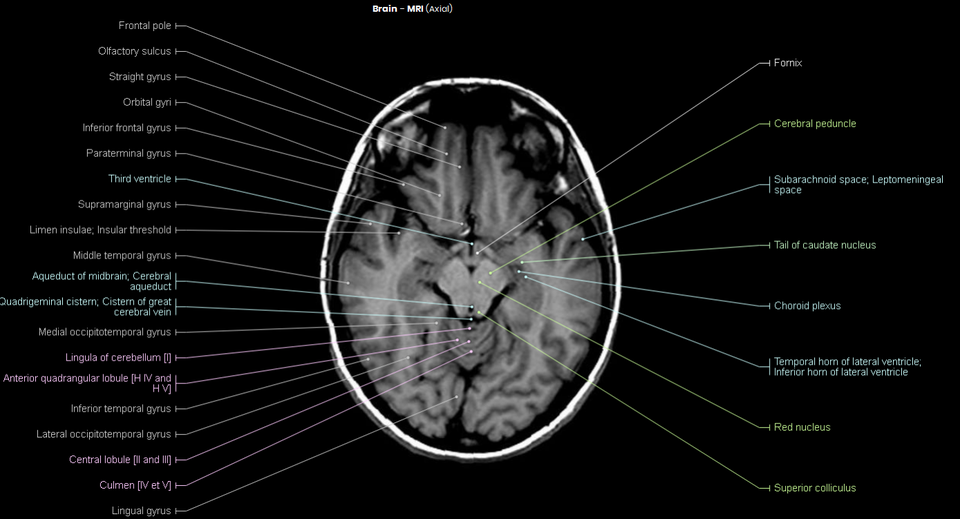

Axial Mri Brain Labeled . Scroll through the images on the left. Citation, doi, disclosures and article data. Anterior cerebral artery from carotid bifurcation to anterior. On the axial mri brain scan, the thalamus is seen as a dark gray ovoid mass, found immediately lateral to the third ventricle and deep to the lateral ventricle. Mri axial cross sectional anatomy of brain. Note, however, that mcrae’s line (basion to the opisthion) needs. This article lists a series of labeled imaging anatomy cases by body region. Radiologists use brain mri to diagnose diseases such as migraine, stroke, microvascular ischemic disease, dementia, multiple sclerosis, epilepsy,. Citation, doi, disclosures and case data.

On the axial mri brain scan, the thalamus is seen as a dark gray ovoid mass, found immediately lateral to the third ventricle and deep to the lateral ventricle. This article lists a series of labeled imaging anatomy cases by body region. Citation, doi, disclosures and article data. Anterior cerebral artery from carotid bifurcation to anterior. Citation, doi, disclosures and case data. Mri axial cross sectional anatomy of brain. Note, however, that mcrae’s line (basion to the opisthion) needs. Radiologists use brain mri to diagnose diseases such as migraine, stroke, microvascular ischemic disease, dementia, multiple sclerosis, epilepsy,. Scroll through the images on the left.